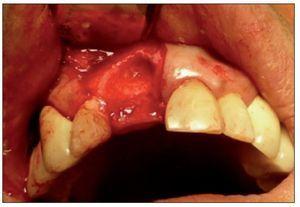

Figura 3. Sitio quirúrgico posexodoncia.

Figura 4. Colocación del injerto óseo previa fijación de la membrana.

Figura 5. Estabilización del injerto de tejido conectivo sobre la membrana.

Figura 10. ROG más injerto de tejido conectivo.